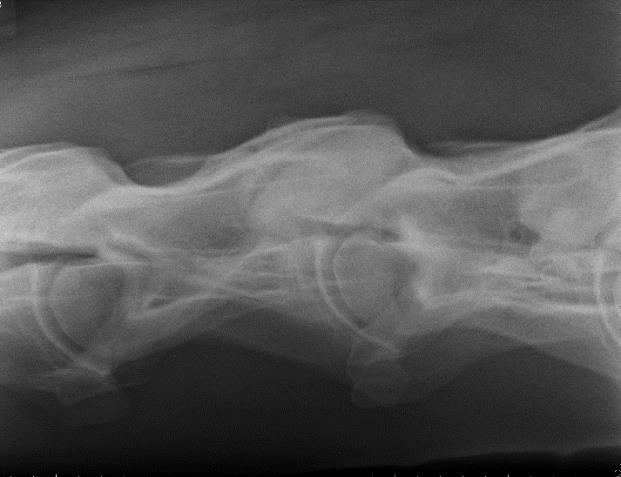

The development and advancement of digital radiography has allowed for diagnostic field radiographs of the neck and some parts of the thoracolumbar spine. Lateral images of the cervical spine may demonstrate the presence of osteoarthritis, vertebral anomalies, and abnormalities of the vertebral canal, such as stenosis. One can also acquire very diagnostic oblique images of the cervical articular processes with practice (Figures 2A and 2B).

RFigure 2A: Field radiograph using portable machine and DR technology demonstrating enlargement of an articular process joint. Cranial is to the left.

Fig. 2A: Field radiograph using portable machine and DR technology demonstrating enlargement of an articular process joint. Cranial is to the left.

Image courtesy of Dr. Richard D. Mitchell.

Figure 3: Oblique thoracic image of a 16.2 hand Warmblood, 84 KVP/.18 sec with a portable generator, demonstrating marked, multifocal, ventral spondylosis. In the author’s experience, such lesions may be associated with stiffness and poor performance. Image courtesy of Dr. Richard D. Mitchell.

Fig. 2B: Field radiograph using portable machine and DR technology demonstrating articular process osteoarthritis (oblique view). Cranial is to the left

Figure 2B: Field radiograph using portable machine and DR technology demonstrating articular process osteoarthritis (oblique view). Cranial is to the left.